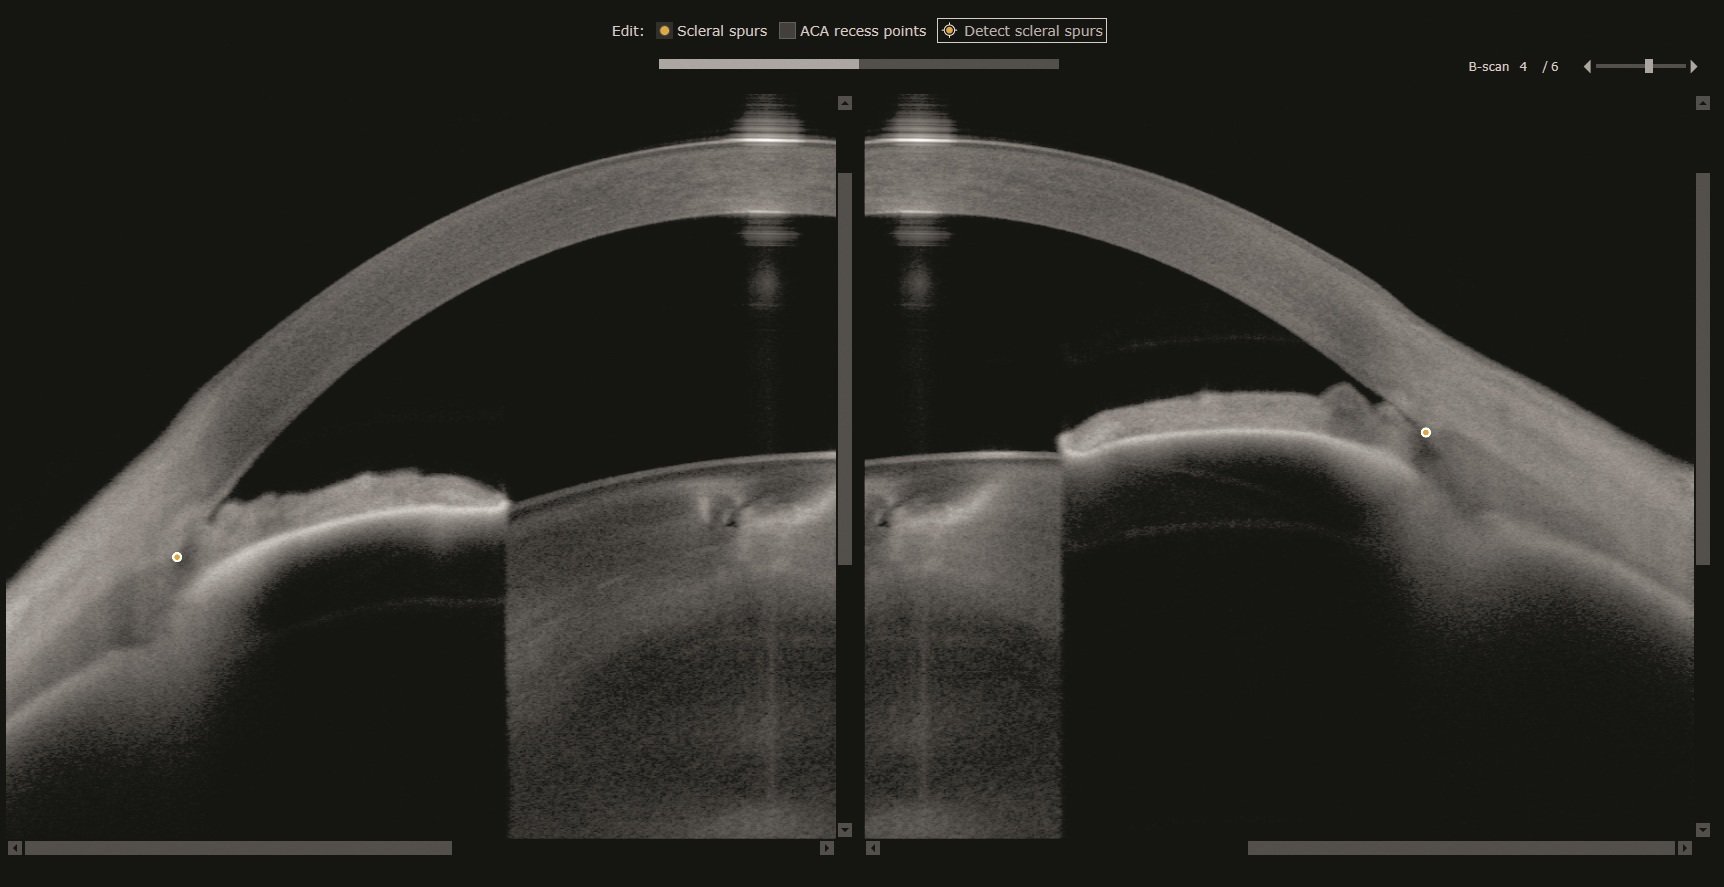

Als unverzichtbares Werkzeug für die Planung von Kataraktoperationen ermittelt ANTERION präzise biometrische Streckenmessungen sowie die gesamte Hornhautstärke, alles mit optimierter OCT-Technologie. So können Sie Ihre klinischen Ergebnisse selbst in den schwierigsten Fällen verbessern. Die OCT-Bilder helfen Ihnen dabei, Ihre Messungen zu bestätigen, sodass weniger Annahmen erforderlich sind.

Die Cataract App bietet sphärische und torische IOL-Berechnungen sowie Raytracing-Anwendungen und liefert die erforderlichen Daten zur Berechnung der für Ihre Patient:innen am besten geeigneten IOL, ohne dass Daten übertragen oder Geräte gewechselt werden müssen.